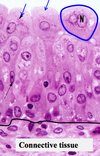

Transitional epithelium (Uroepithelium) Stratified and dome cells at apical surface